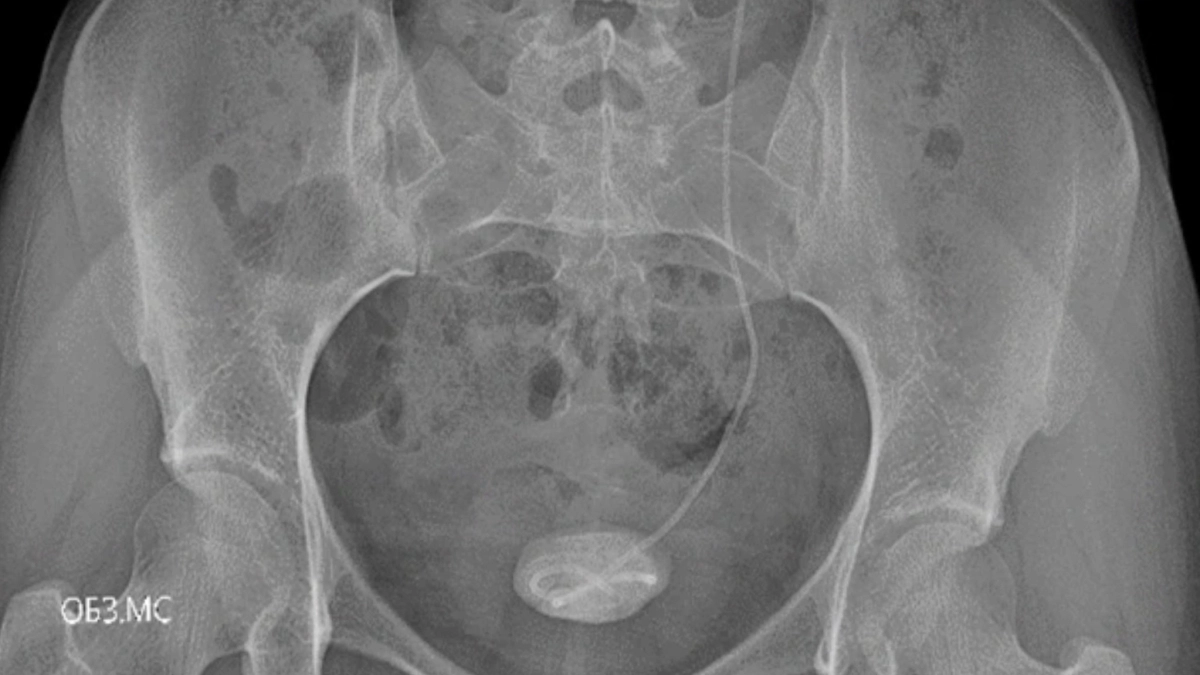

Ярославские врачи помогли 18‑летней девушке, у которой в мочевыводящих путях полгода оставался установленный ранее стент. Пациентка поступила во второе урологическое отделение клинической больницы №9 с комплексом осложнений после установки мочеточникового стента в другой медицинской организации: она не явилась на плановое удаление через шесть недель и не наблюдалась у специалистов, из‑за чего на стенте появились отложения солей и образовались камни в мочевом пузыре и почке. об этом рассказал портал "СОРОКА" со ссылкой на больницу.

Для лечения потребовался поэтапный хирургический подход с использованием современного эндоскопического оборудования. Сначала врачи выполнили контактную цистолитотрипсию с применением гольмиевого лазера: этим методом раздробили камень в мочевом пузыре, постарались уменьшить травму тканей и дополнительно обработали участок, где долго находился стент. Такой малоинвазивный формат вмешательства позволил работать прицельно и снизить вероятность дополнительных повреждений.

На втором этапе с помощью того же гольмиевого лазера специалисты аккуратно удалили стент, устранили последствия его длительного нахождения в организме и выполнили дробление с последующим удалением камня в почке. Лазерная технология дала возможность провести вмешательства с минимальной травмой, обеспечить более быстрое восстановление и уменьшить риск осложнений. Операции выполнили заведующий 2‑м урологическим отделением Артём Крохмалёв, ординатор отделения Александра Васильева и врач‑уролог высшей категории Дмитрий Федотов. Пациентка успешно завершила лечение и была выписана в стабильном состоянии с рекомендациями по дальнейшему восстановлению.